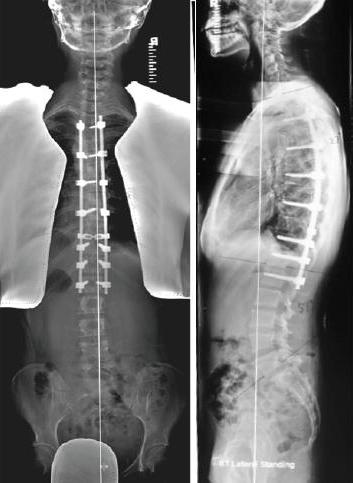

Surgery: (Figs. 8-10) For the very small number of children with severe curves, internal fixation is applied to the spine to correct the curve within the limits of safety. Surgery for scoliosis has been made very safe by major advances in surgical techniques including surgical navigation and the use of intraoperative spinal cord monitoring [1,6,7,8].

![]() Fig. 8 AP and Lateral radiograph showing right thoracic curve before surgery. |

![]() Fig. 9 Posterior spinal fusion with thoracic pedicle screws. Note spontaneous correction of compensatory lumbar curve. Lumbar spine motion is preserved. |